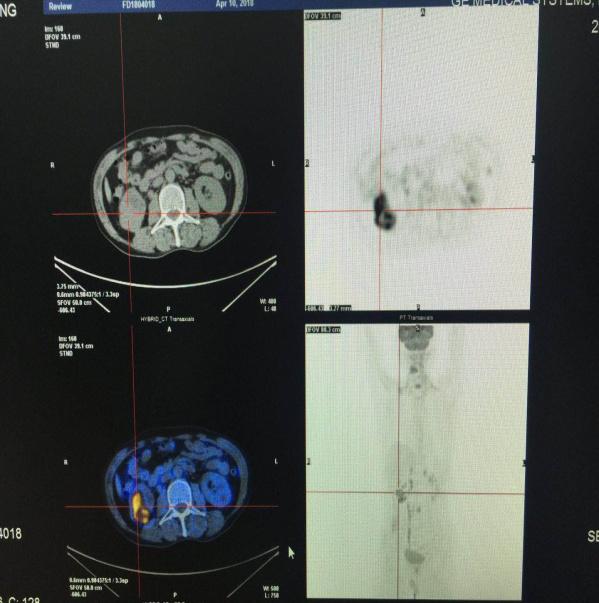

病情发展到一个月前,阿忠开始出现新的症状,除了颈椎疼痛加重,相继出现有大腿和腰痛。辗转当地多家医院,经CT与核磁等各项检查后,考虑多发骨转移瘤可能,但未找到原发灶,也就是我们俗话说的不知道是啥病。近期在我院就诊,入院常规检查后,大夫决定行PET/CT全身显像检查。令人欣慰的是,PET/CT确实给力,得到了明确的诊断,找到了折磨阿忠许久的病因——考虑右肾恶性肿瘤,全身多发骨转移瘤。以下是阿忠的PET/CT检查部分截图,能够很明确地看到在肾脏上有异常,并且累及之前所述的颈椎、胸椎和腰椎。虽然阿忠病情不容乐观,但找到了病因,且具有手术机会,经过术前的必要检查,已拟行手术治疗。